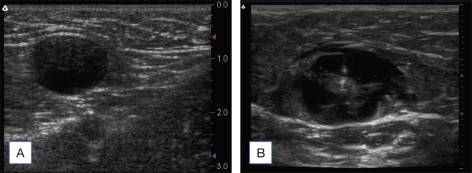

ELA and CF is usally performed with a dilute tumescent anesthetic solution of Lidocaine in normal saline (a concentration of 0.1% lidocaine is typically used with an average volume of about 5–10 mL/cm of treated vein) with or without epinephrine, often buffered with sodium bicarbonate. This should be delivered with ultraound guidance into the perivenous space (saphenous sheath) of the vein to be treated. If can be injected either manually or with an infusion pump such that upon completion of the process the vein is surrounded along its entire treated length with the anesthetic fluid as demonstrated in Figure 9.1 .

Set the laser to continuous mode and select the power to be used. Re-verify placement of the laser tip with ultrasound ( Fig. 9.4 ).

Figure 9.4

Longitudinal (sagital) ultrasound image of the saphenofenoral junction demonstrating a 400 micron laser fiber tip in the great saphenous vein (GSV) just below the superficial epigastric vein (SEV). FV, femoral vein